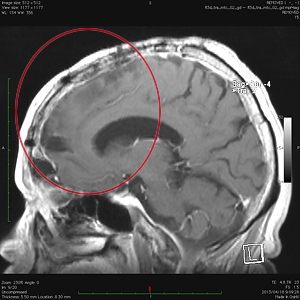

悪性腫瘍の手術前

手術後

放射線・化学療法後